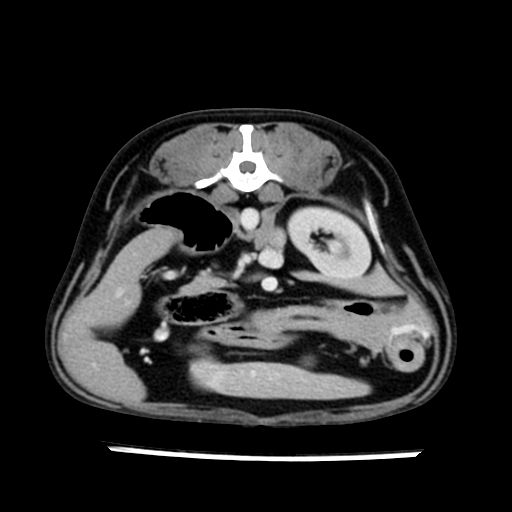

prescritto esame TAC

sequenza immagini limitata al fegato reni e surreni

le immagini ecografiche rispetto alla tac datano circa 7 mesi prima ,le surrenali sono normali nonostante il test acth sia risultato positivo .all’esame TAC dopo diversi mesi risultano aumentate armonicamente nel volume e si individua un forte sospetto di adenoma ipofisario .

sospetto adenoma ipofisario vs. meno probabilmente meningioma della base; intertiziopatia polmonare; lesione espansiva epatica, verosimilmente del lobo laterale sinistro, di sospetta natura neoplastica; lesioni spleniche di natura da definire; iperplasia/ipertrofia delle ghiandole surrenali, bilateralmente; vertebra di transizione del rachide toracico; tenosinovite cronica del muscolo bicipite brachiale di destra.